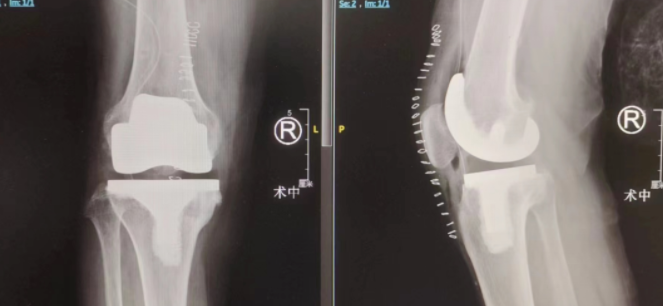

在betway在线登陆关节外科,副主任医师郝亮为王钢进行了仔细检查,X线显示其膝关节退变,关节间隙明显变窄,并出现跛行、膝关节内翻、肿胀等明显症状,综合判断其为“右膝关节骨关节病”。

在经过相关术前讨论及手术准备后,郝亮、蒋涛、王琳手术团队决定为其进行智能导航下右侧人工膝关节置换术。依靠智能导航的精准定位,医生可以在数字化场景下进行截骨及安装假体——术中各项指标通过影像及数据展现在主刀医生面前,相较于传统手术只能依靠个人经验来判断的方法来说,对患者的手术安全更有保障!

手术很顺利,仅用1小时便顺利完成。术后第二天,王钢就可以下床进行简单活动,随后通过系统的康复训练,很快就可以回归正常生活。